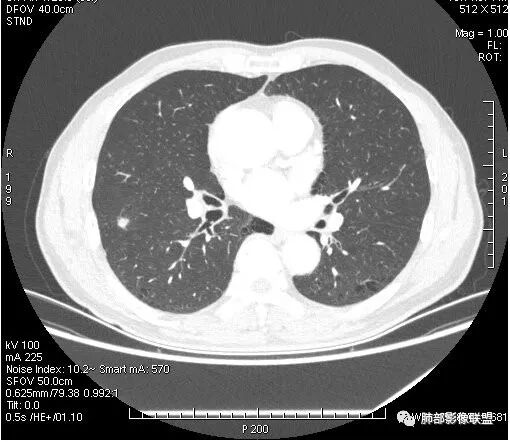

患者右上肺占位,内部强化不均,有空泡,有血管穿过,血管聚集现象,似有胸膜牵拉,考虑恶性

右肺上叶后段占位病灶,病灶不规则,周围胸膜线性牵拉,病灶部分周围有晕,病灶内见不规则空洞,未见明显引流支气管,长毛刺,多分叶、肿块边缘部分L型,可见血管直接供养。增强见点状坏死、病灶内血管。综上考虑恶性可能性大,鉴别隐球菌。

右肺上叶结节,浅分叶膨隆,边缘可见胸膜牵拉及血管集束,不规则厚壁空洞,不均匀强化,血管进入病灶,边缘毛燥,考虑低分化腺癌,鉴别隐球菌。

来个不一样的,小病灶近心端空洞,分叶,毛刺软,长,收缩力差,强化明显,血管走形自然,无明显卫星灶,先考虑炎性,肉芽肿炎,隐球菌可能性大,不排除肿瘤,需要活检

右肺团块影,深分叶,有毛刺,但毛刺偏软。团块附近有血管走行,穿过。血管增粗,僵直。空洞近心,团块周围似有卫星灶。良,恶性征象都有;按可能性排序:隐球,结核,腺癌。

右肺结节,分叶、长短毛刺,边缘略膨隆,胸膜牵拉,血管进入病灶,收缩力较弱,有血管聚集征,洞壁尚规整,低强化,坏死边缘规整。考虑炎性,隐球,鉴别腺癌。

晨读,右肺上叶结节,边缘膨隆、分叶,部分边缘有平直,可见多发毛刺及胸膜牵拉,牵拉线清秀,收缩力弱,内密度不均,可见片状低密度影及空洞,增强后不均匀强化,血管集束,考虑良性,肉芽肿性结节,鉴别腺癌

晨读:双肺胸膜下多发小气囊,大小不一,右肺结节,内部可见小空洞,洞壁光滑,厚薄不一,偏心性生长,近段血管束增粗,有分叶,毛刺(软),有晕征,平扫密度尚可,增强后不均匀强化,可见低密度坏死,及部分血管穿行,体检发现,考虑恶性:腺癌,鉴别炎性结节

晨读:右肺中叶结节,浅分叶,边缘膨隆,胸膜牵拉,不规则偏心厚壁小空洞,空洞壁可见低密度坏死,不均匀强化,血管进入病灶,边缘毛燥,考虑鳞癌。鉴别肉芽肿

右肺上叶结节,边界清,有分叶,厚壁空洞,强化后见坏死区,血管进入病灶,考虑结核。

右上叶结节,轻分叶,结节有长短不一毛刺,结节周围GGO边界清,有血管集束征,肺窗结节周围似可见卫星灶,可见鬼脸征,良恶性征象都有,但GGO边界清,浸润性腺癌耍考虑,临床症状轻微,体捡发现,似可见卫星灶和鬼脸征,炎性肉芽肿TB或隐球菌要鉴别。

影像学改变:

1.右肺上叶后段类圆形结节影,密度不均,有坏死空洞,坏死比较彻底,内外壁都较清楚。

2.病灶有浅切迹,没有深分叶,毛刺大多细长且柔软。

3.可见棘状突起及胸膜牵拉,但未见胸膜凹陷。

什么意思?结节影有牵拉的动作,但似乎“出工不出力”,收缩力羸弱!

4.病灶轻到中度强化。病灶内血管走行较完好,病灶旁血管局部显示粗大。

5.支气管关系不确定。

6.灶周见小结节影(卫星灶),边界不甚清晰。